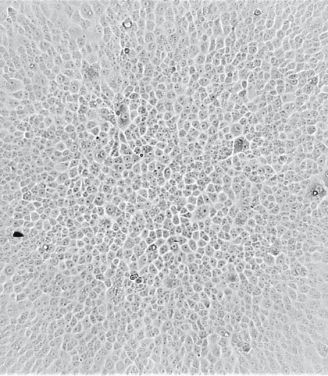

To test the ability of vaccine recipients' serum antibodies to neutralize the Omicron variant, the team used sera from two groups of vaccine recipients who have received two doses of BNT162b2 (BioNtech) or Coronavac. Each group consists of 25 people.

Two Omicron variants present in Hong Kong were tested, one from South Africa and the other from Nigeria (with the additional R346K mutation). The ability of serum antibodies to neutralize the Alpha, Beta, and Delta strains was also tested as a control.

Only five out of 25 Biontech vaccine recipients had neutralizing ability against the Omicron variant virus, and the vaccine efficiency was significantly reduced to 20 - 24%. Compared to the original SARS-CoV-2 strain, the titer of neutralizing antibodies against the Omicron variant has decreased by 36 - 40 fold.

None of the serum of the 25 Coronavac vaccine recipients contain sufficient antibody to neutralize the Omicron variant at the limit of 1 in 10 dilution.